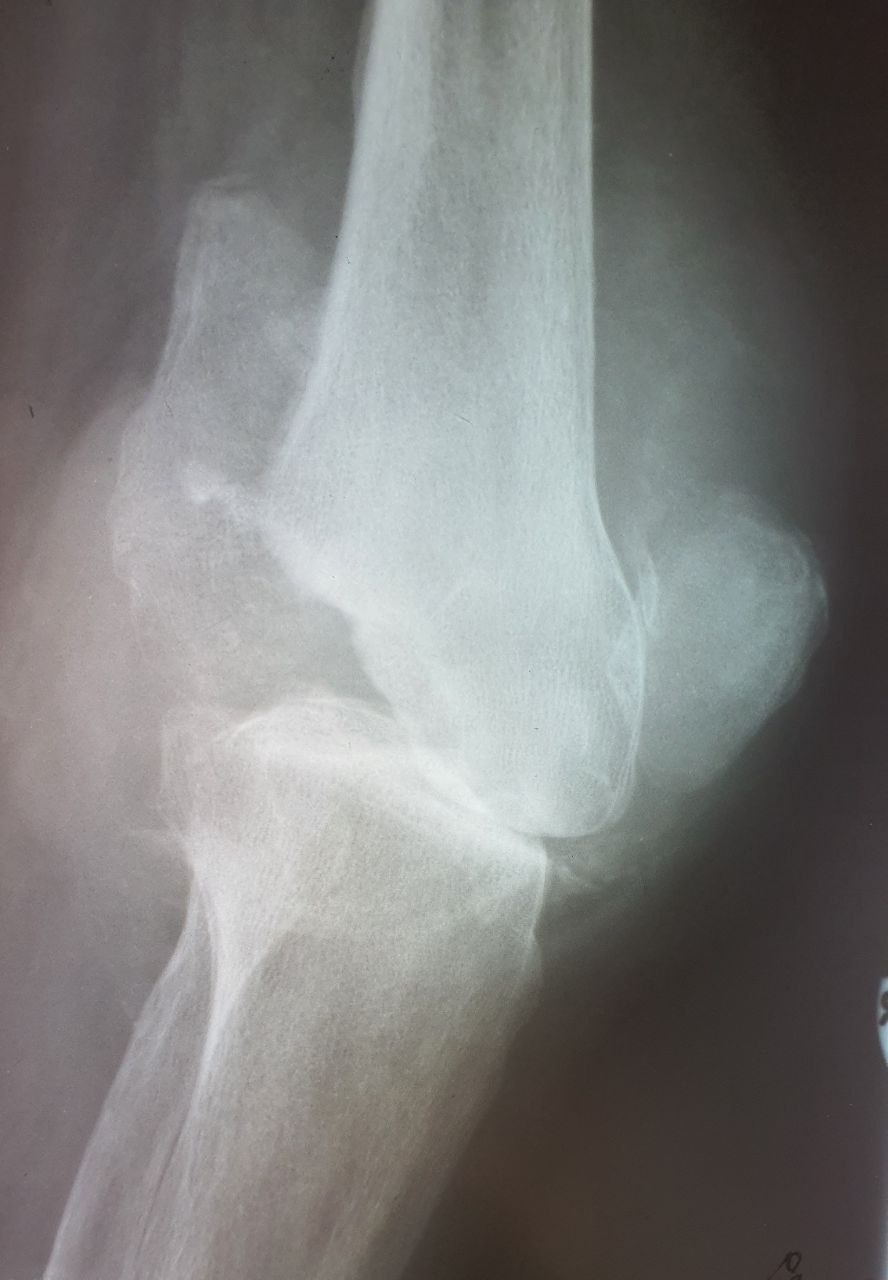

Есть сомнения, а возьмут ли его на эндопротезирование. С таким дефектом...

Становилась в очередь на операцию, по квоте, по поводу ДОА 3 ст.  Первичных снимков я не видел.